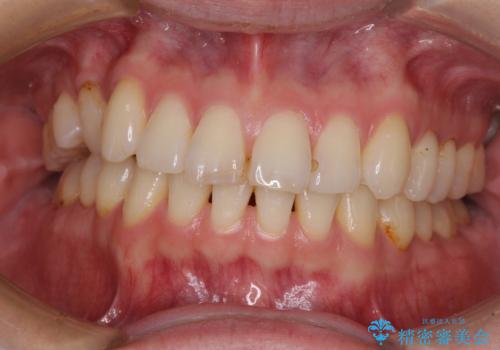

- 以前矯正治療を行ったものの、思い通りの仕上がりではなく、更には後戻りが気になってきたとのことで来院された患者様です。

上顎右側の第一小臼歯が動きにくい歯であり、以前矯正治療を行った際に傾斜した位置のまま終了したことと、それに伴い後戻りで歯列が波打っているようになっていることを大変気にしていらっしゃいました。